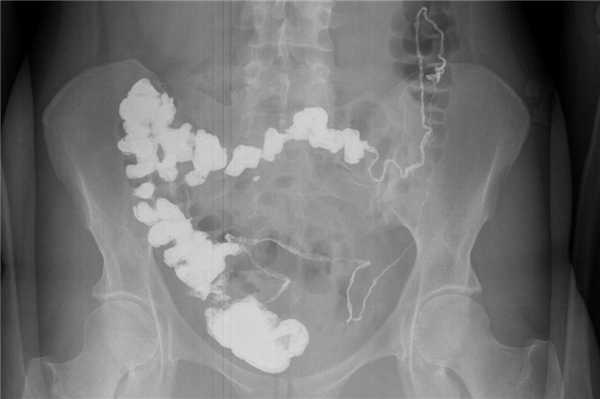

Введение рентгеноконтрастного вещества в верхние отделы ЖКТ (через рот или назогастральный зонд (НГЗ)) с получением серии рентгенограмм для исследования продвижения контраста по тонкой кишке в толстую.

а) Преимущества пробы Шварца:

• Оценка анатомических особенностей, конфигурации, диаметра, длины (например, после предшествующих резекций), стриктур, свищей, изменений слизистой и т.д.

• Оценка функции: время пассажа, замедленное продвижение контраста.

• Выявление уровня обструкции.

б) Ограничения пробы Шварца. Ограниченные возможности для оценки состояния слизистой по причине наложения петель друг на друга.

б) Оборудование и методика. Обзорный снимок. Назначение одного стакана жидкого бария внутрь => серия снимков в соответствующие интервалы времени. Если контраст не достиг толстой кишки в течение 4 часов => поздние снимки (например, через 24 часа).